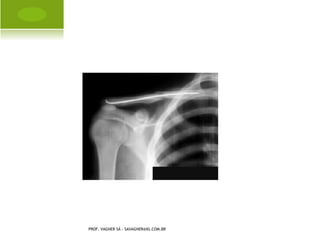

L UXAÇÃO O MBRO

PROF. VAGNER SÁ - SAVAGNER@IG.COM.BR

L UXAÇÃO A CRÔMIO -

C LAVICULAR

F RATURA - LUXAÇÃO OMBRO